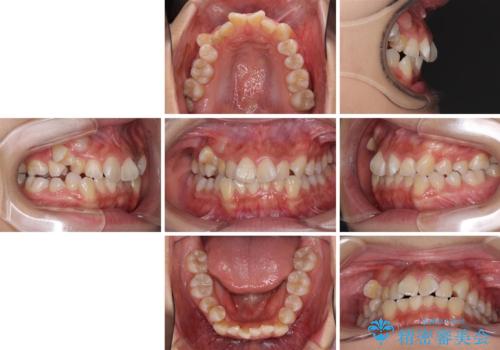

- 前歯のでこぼこと乳歯が残るほどの八重歯を気にして来院された患者様です。

非抜歯にてワイヤー矯正にて治療することとしました。(ただし、親知らずと乳歯は抜歯)

犬歯は歯根が太く長いため、移動には時間を要します。しかし、犬歯は機能面から考えて残すことを選択したいため、長期間をかけて治療を行うこととしました。

治療の度に歯列が改善していったため、長期間の治療も楽しく過ごしていいただき、満足のいく仕上がりとなりました。